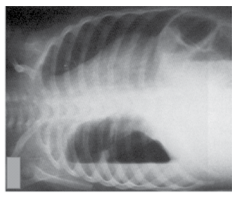

A imagem a seguir representa qual exame do tórax?